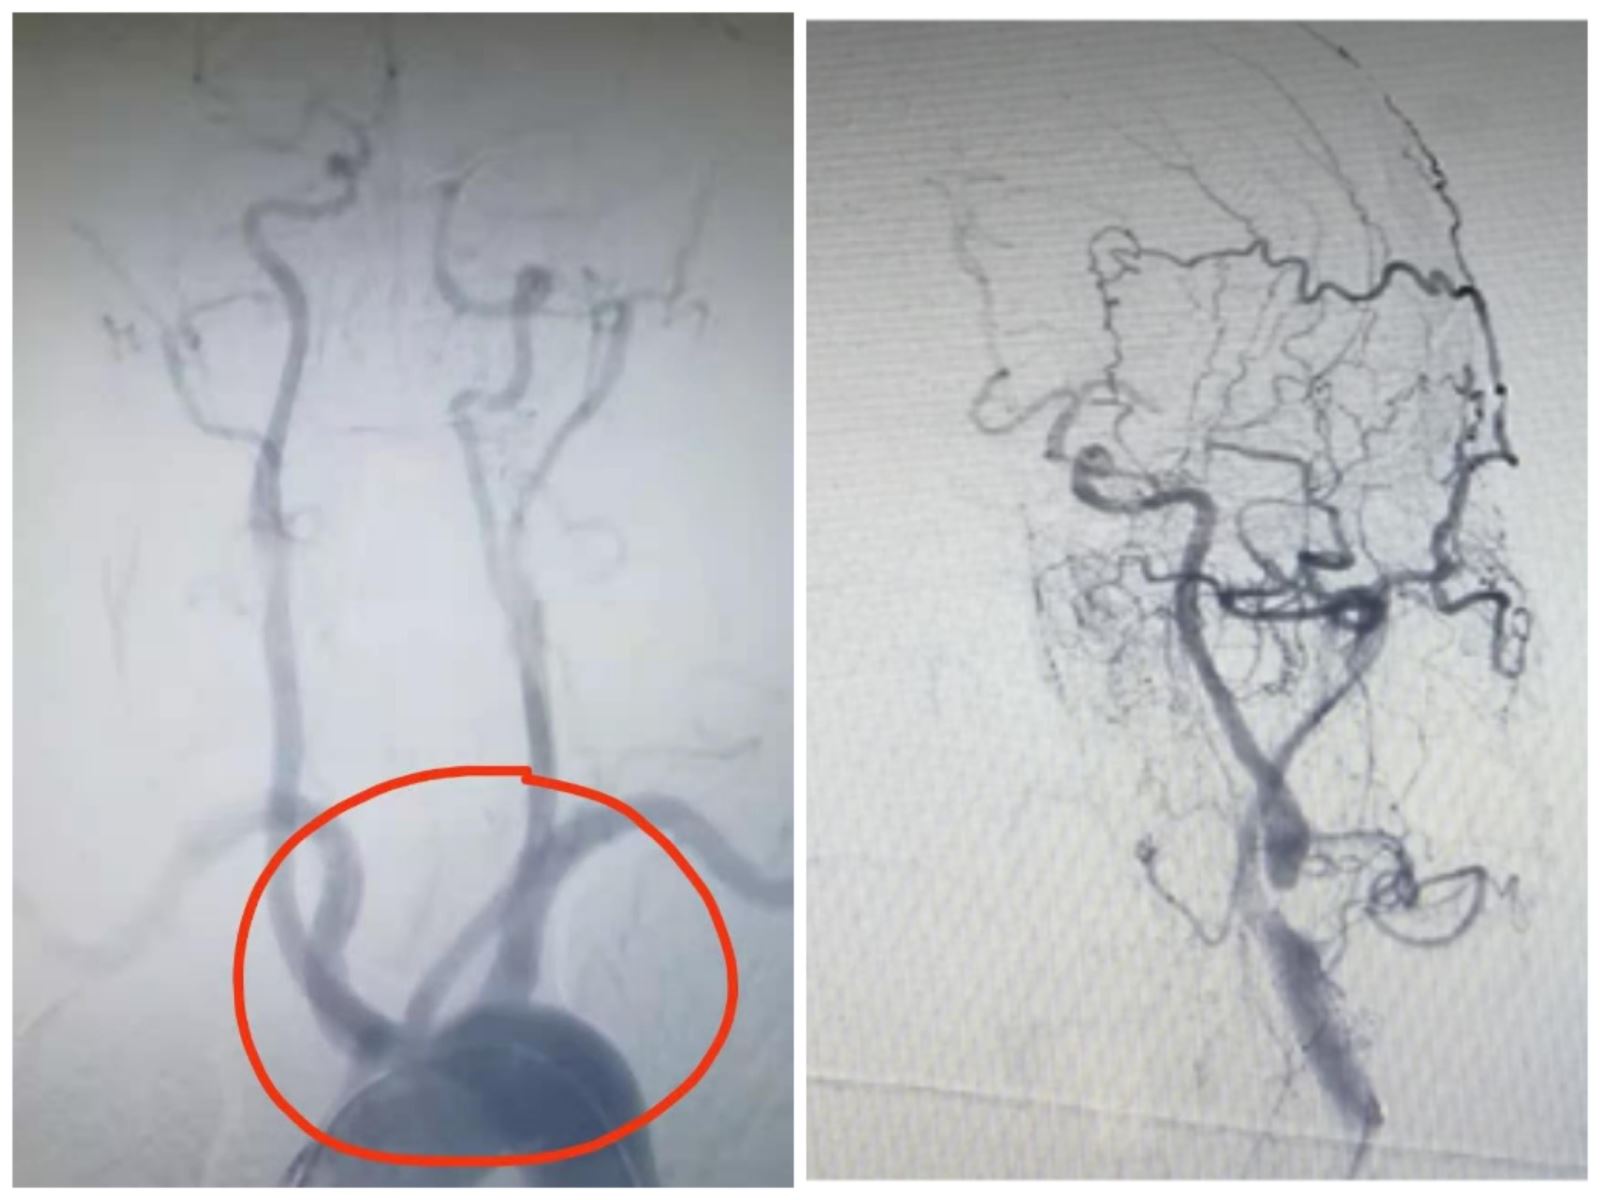

时间紧迫,手术中张国锋与副主任医师徐耀铭争分夺秒,在11:50分完成了动脉穿刺,并进行了全脑血管造影,然而造影结果并不乐观,患者血管畸形发育:右侧迷走锁骨下动脉,右侧颈内动脉和左侧颈内动脉弓上共干,左侧颈内动脉重度狭窄,左侧椎动脉重度狭窄,右侧椎动脉V4段闭塞,左侧大脑前动脉通过脑膜支向左侧大脑中动脉分布区供血,手术难度较大。二位医生合力先使用2mm×12mm的小球囊扩张左侧颈内动脉起始段,再使用4mm×30mm的大球囊扩张后,行颈动脉支架植入术。导引导管通过支架后,微导丝带微导管通过左侧大脑中动脉闭塞段,证实真腔,撤除微导丝,取栓支架到位后释放支架,取出血栓后大脑中动脉血流明显改善。近6个小时的手术,手术过程险象迭生,患者血管再通。患者术后第7天仅留有轻微面瘫及言语不利,NIHSS2分,预后良好。患者家属对治疗效果非常满意,并表达了对参与救治医护人员的感谢。